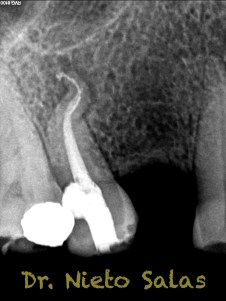

Y  de forma muy similar en el caso B; en este caso el paciente vino a la revisión a los 9 meses evidenciado el éxito en el tratamiento:

La verdad, no me planteé la posibilidad de la obturación con Thermafil, se trataba de un caso con un sistema de conductos con un itsmo coronal, y pienso que la obturación con sistema de ola continua me garantizaba un mejor sellado.